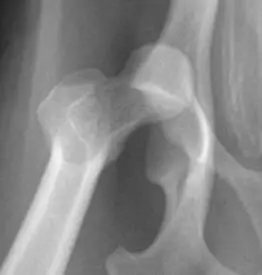

2. 고관절 구조와 수술의 원리

고관절은 대퇴골의 머리(볼)가 골반의 소켓에 맞물려 있는 구조로, 강아지의 뒷다리를 지지하는 중요한 관절입니다. 하지만 이 부위에 손상이 생기면 통증과 운동 제한이 심해지며, 보행이 어려워질 수 있습니다.

FHNO 수술을 통해 대퇴골 머리를 절제하면 볼-소켓 구조는 사라지지만, 시간이 지나면서 근육과 섬유 조직이 새로운 연결을 형성해 '거짓 관절' 역할을 하게 됩니다.